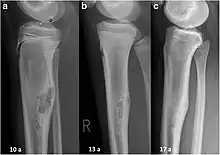

Non-ossifying fibroma of tibia

An arm bone tumor